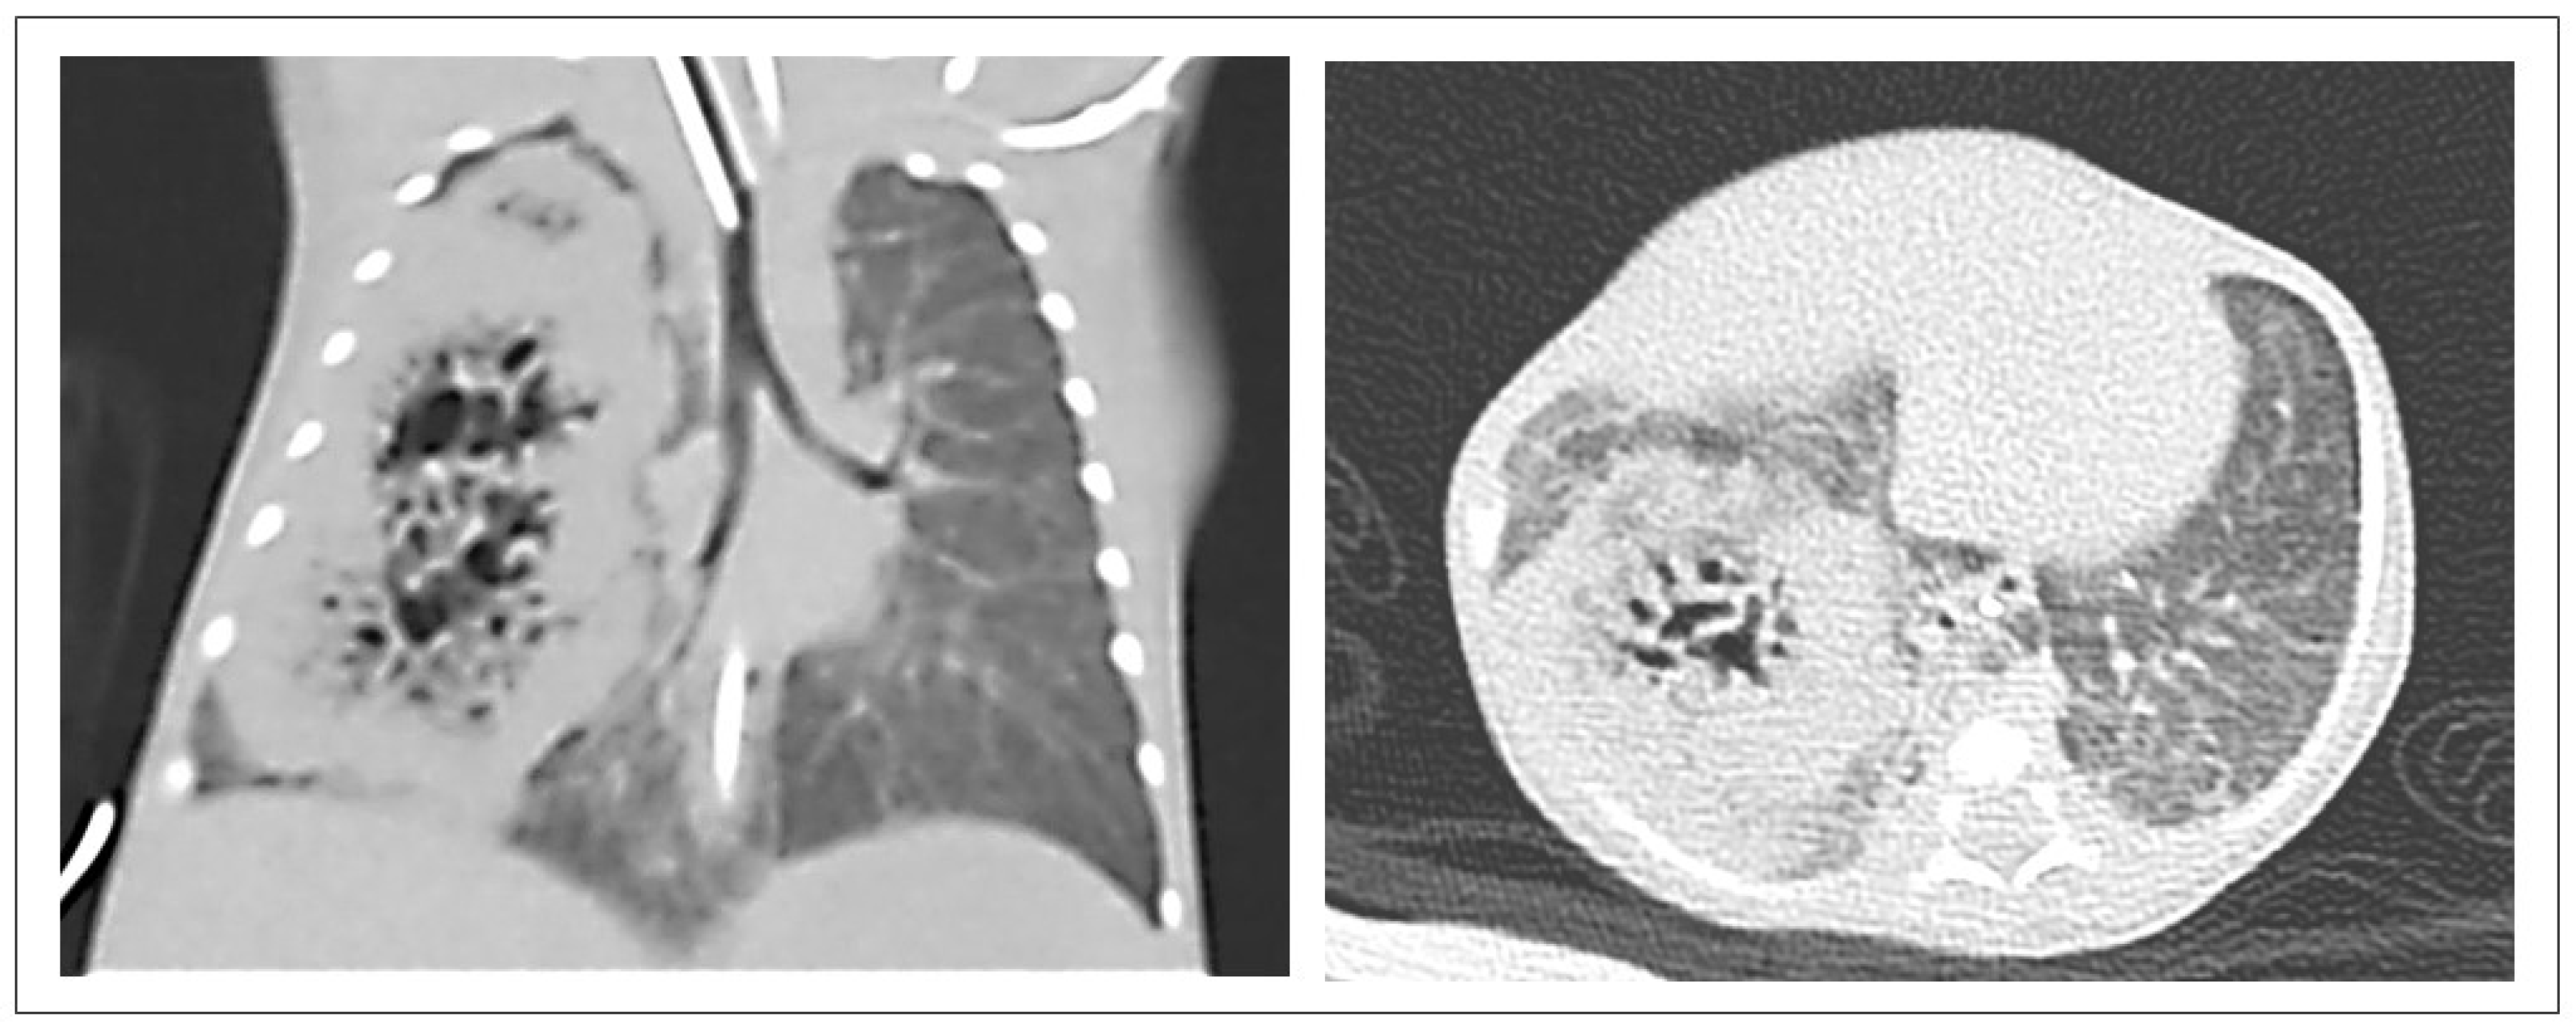

3.2. CPAM CT Findings

4.2. CPAM CT Findings